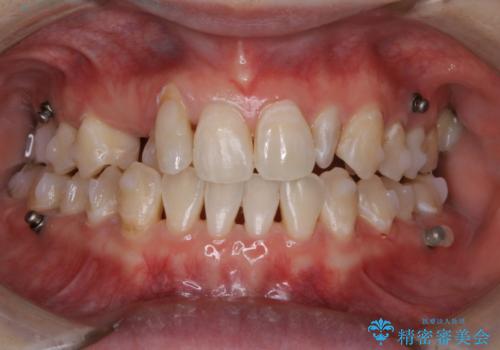

ワイヤー矯正終了時に装置除去と合わせてPMTC

担当医 歯科衛生士